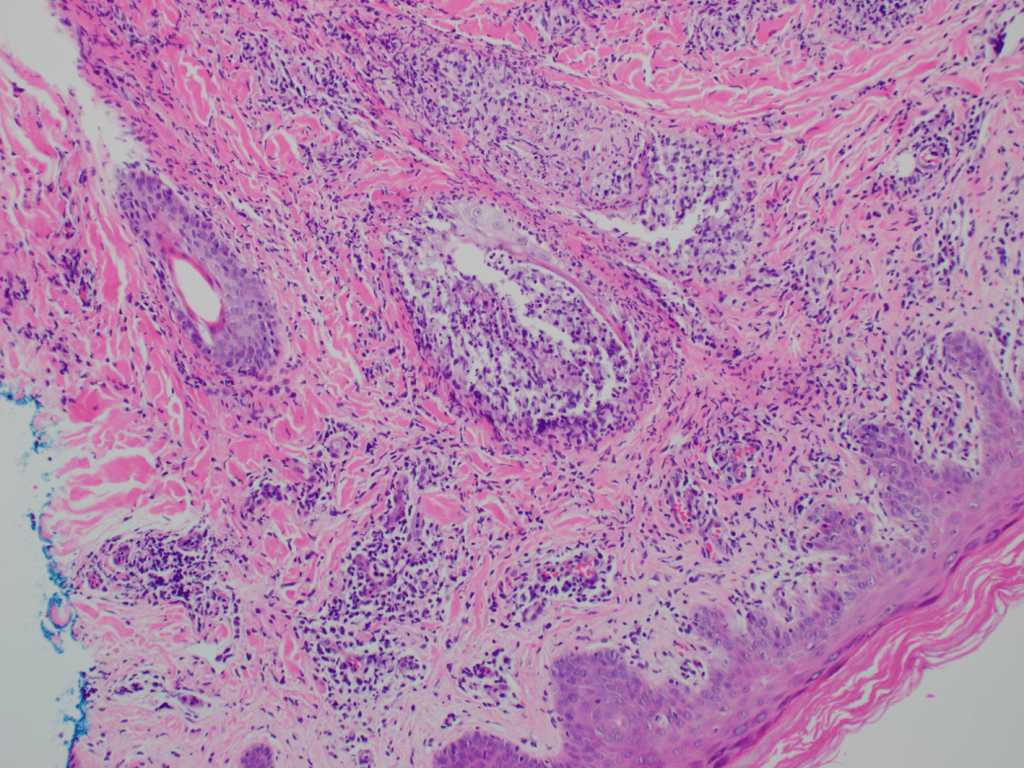

An adult patient with no significant past medical history presents with a tender right inguinal mass and rash over the right buttock measuring 5×7 cm. A skin punch biopsy was performed on the gluteal rash and sent to histopathology for analysis. Histology (Image 1) revealed an intradermal acantholytic vesicular dermatitis and associated folliculitis. Chronic inflammatory infiltrates surrounded neurovascular bundles as well as adnexal structures. Multinucleated Tzank cells were identified with the characteristic multinucleation, margination, and molding. Scattered eosinophilic Cowdry A inclusions were seen. Stains for bacteria and acid-fast bacilli (AFB) were not performed. A periodic acid-Schiff (PAS) stain (Image 2) demonstrated the absence of fungal elements.

The histology of VZV infection is characterized by intradermal and sub-epidermal vesicles with associated acantholysis, necrosis, and spongiosis. Tzanck cells demonstrate the characteristic “3 Ms” of multi-nucleation, marginated chromatin, and nuclear molding. The dermis is notable for perivascular, periadnexal, and perineural lymphocytic infiltrates. Folliculitis and syringitis may be present along with small vessel necrotizing vasculitis. Late stage lesions are notable for encrusted ulcers. Though there is significant histologic overlap between VZV infection as those caused by others in the herpes family, VZV histology tends to demonstrate a more substantial follicular involvement.2 Besides other herpes viruses, the differential diagnosis includes erythema multiforme, coxsackievirus, ecthyma contagiosum, pemphigus vulgaris and paravaccinia infection.3